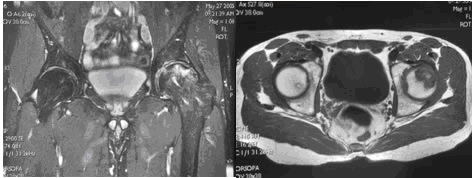

La risonanza magnetica è considerata la metodica d’indagine più accurata per quantificare l’area osteonecrotica in fase precoce e per individuare la sede topografica della lesione, con una sensibilità che oscilla fra 88 e 100 % grazie alle caratteristiche di multiplanarietà e multiparametricità. La RMN, infatti, valuta l’area interessata su 3 piani: trasversale, coronale sagittale ed, inoltre, permette di discriminare la componente ossea da quella cartilaginea, evidenziando un’eventuale condropatia.

In particolare, lo stadio della patologia viene classificato secondo la classification de recherche osseous (ARCO) in 4 livelli basati su reperti radiografici e di risonanza magnetica.